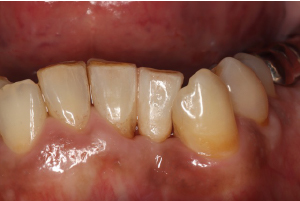

症例

歯周外科+オールセラミック

治療前

治療後

矢印で示している歯の変色と前歯が全体的に短く見えるのが気になるとのことでした。前歯部の歯肉を下げる手術を行い、変色歯はオールセラミックで修復しました。